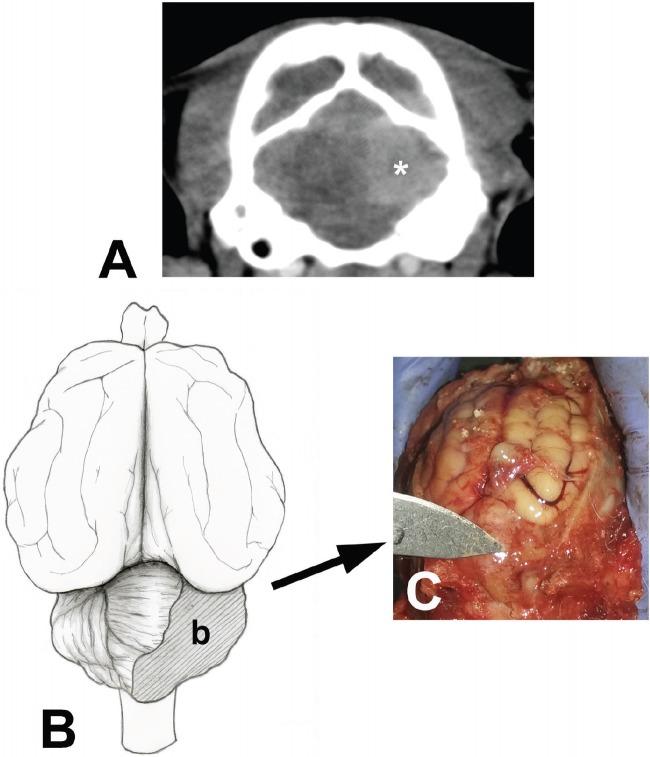

Here, we report an 8-month-old male domestic cat with altered consciousness, symmetric ataxia, hypermetric gait, vertical positional nystagmus, mydriasis, strabismus, intention tremor of the head, and increased patellar reflexes. Neuroanatomical diagnosis suggested a multifocal brain dysfunction (cerebellar and cerebral). The cat tested seropositive for feline leukemia virus. Cerebrospinal fluid analysis indicated mononuclear and neutrophilic pleocytosis. Contrast computed tomography imaging revealed multiple hypodense heterogeneous areas in both cerebral hemispheres, mild ventriculomegaly at the level of the caudal fossa, and a circular sharply marginated, homogeneously hyperdense mass occupying the right cerebellar hemisphere. Postmortem study indicated a 1.1 × 1.3 × 1.2 cm mass in the right cerebellar hemisphere close to the vermis. Histopathological analysis showed diffuse and severe Purkinje cell loss with a decrease in granular cell density and moderate gliosis compatible with CCD. Further, numerous neoplastic lymphoid cells were observed in the infiltrated mass, consistent with a diagnosis of central nervous system (CNS) lymphoma. Immunohistochemistry showed CD20 expression, indicative of a B-cell immunophenotype. In humans, CCD is reported as a rare paraneoplastic syndrome in patients with Hodgkin lymphoma. CNS lymphoma and/or Feline Leukemia Virus (FeLV) infection were both considered as a possible cause of CCD in this case.

在此,我们报告一只8个月大的雄性家猫,出现意识改变、对称性共济失调、步幅过大步态、垂直性位置性眼球震颤、瞳孔散大、斜视、头部意向性震颤以及髌反射增强。神经解剖学诊断提示多灶性脑功能障碍(小脑和大脑)。这只猫检测出猫白血病病毒血清学阳性。脑脊液分析显示单核细胞和中性粒细胞增多。对比计算机断层扫描成像显示双侧大脑半球有多个低密度异质区,尾状窝水平轻度脑室扩大,以及一个圆形、边界清晰、均匀高密度肿块占据右侧小脑半球。尸检研究表明右侧小脑半球靠近蚓部有一个1.1×1.3×1.2厘米的肿块。组织病理学分析显示弥漫性严重浦肯野细胞丢失,颗粒细胞密度降低,中度胶质增生,符合小脑皮质变性。此外,在浸润性肿块中观察到大量肿瘤性淋巴细胞,符合中枢神经系统(CNS)淋巴瘤的诊断。免疫组织化学显示CD20表达,提示B细胞免疫表型。在人类中,小脑皮质变性被报道为霍奇金淋巴瘤患者罕见的副肿瘤综合征。在本病例中,中枢神经系统淋巴瘤和/或猫白血病病毒(FeLV)感染均被认为是小脑皮质变性的可能原因。